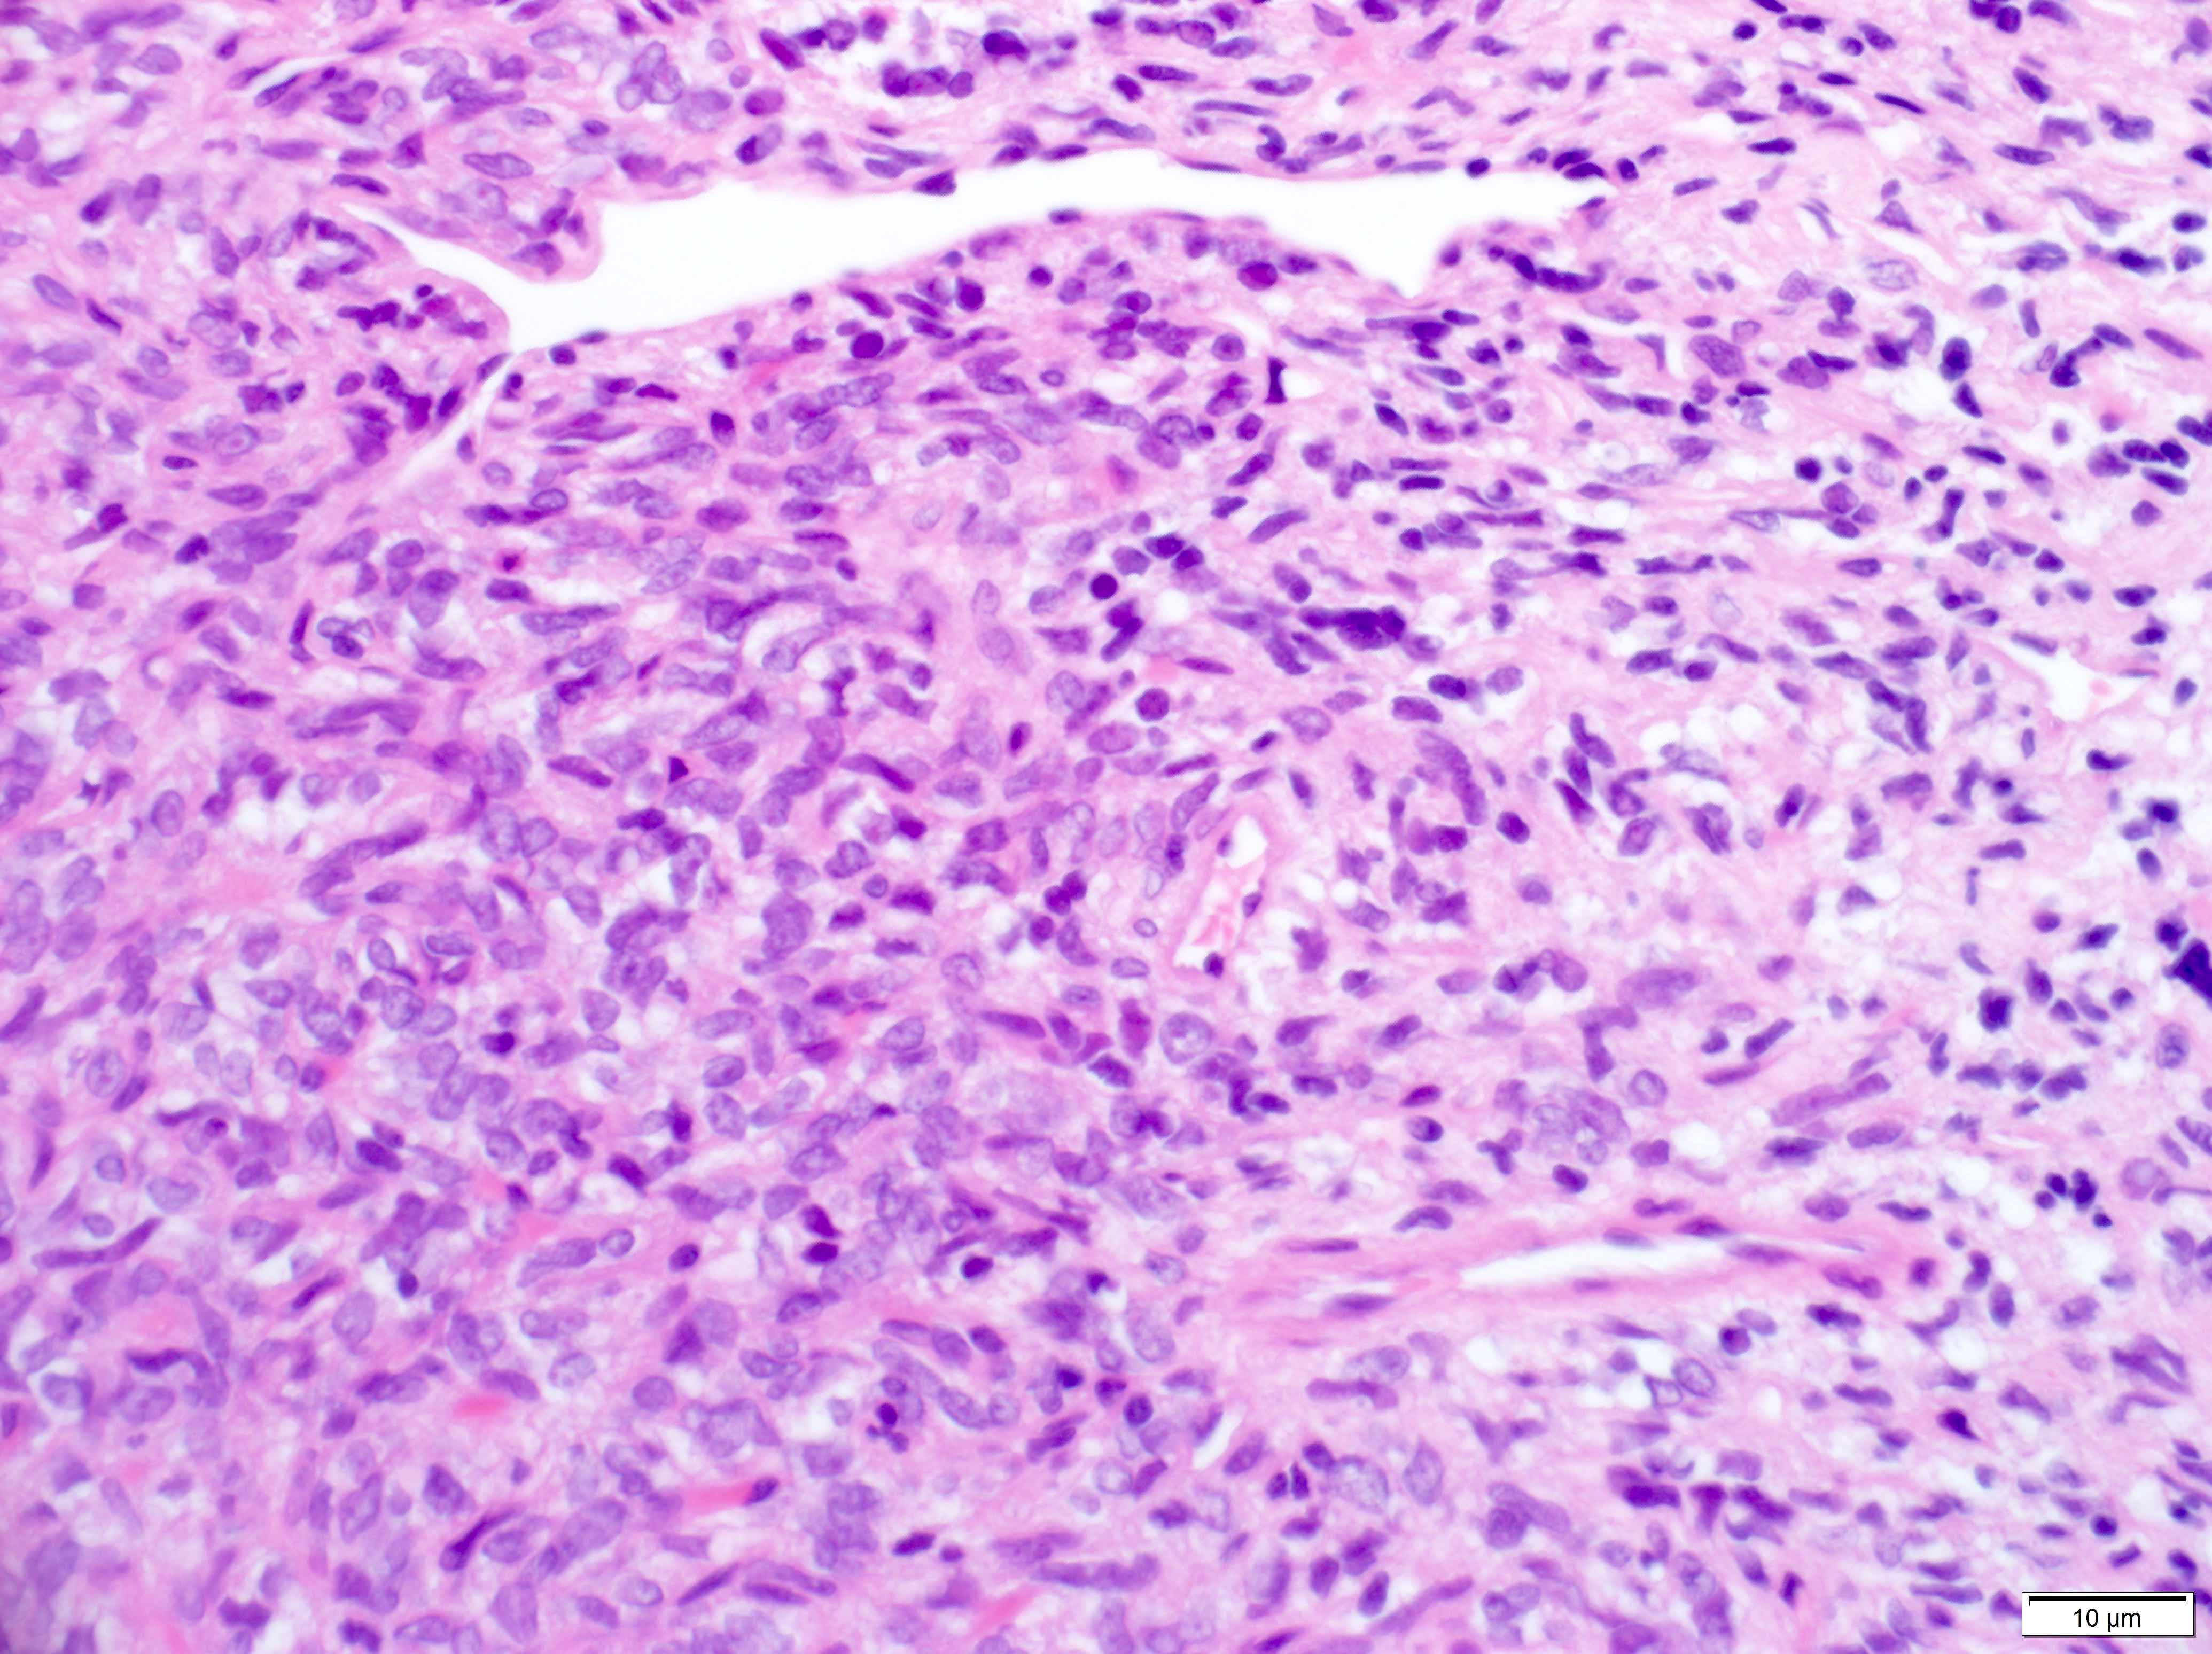

Microscopic (histologic) description

- Essential: patternless pattern of spindle cells, often solid but can also have papillary and other architectures, arranged around branching hyalinized vessels

- Varying amounts of stromal collagen and overall cellularity

- Nuclei are bland, without features seen in mimicking neoplasms

- WHO grading criteria:

- < 5 mitoses/10 high power fields (HPF) = grade 1

- ≥ 5 mitoses/10 HPF = grade 2

- ≥ 5 mitoses/10 HPF with necrosis = grade 3

- Often has staghorn vasculature

Microscopic (histologic) images